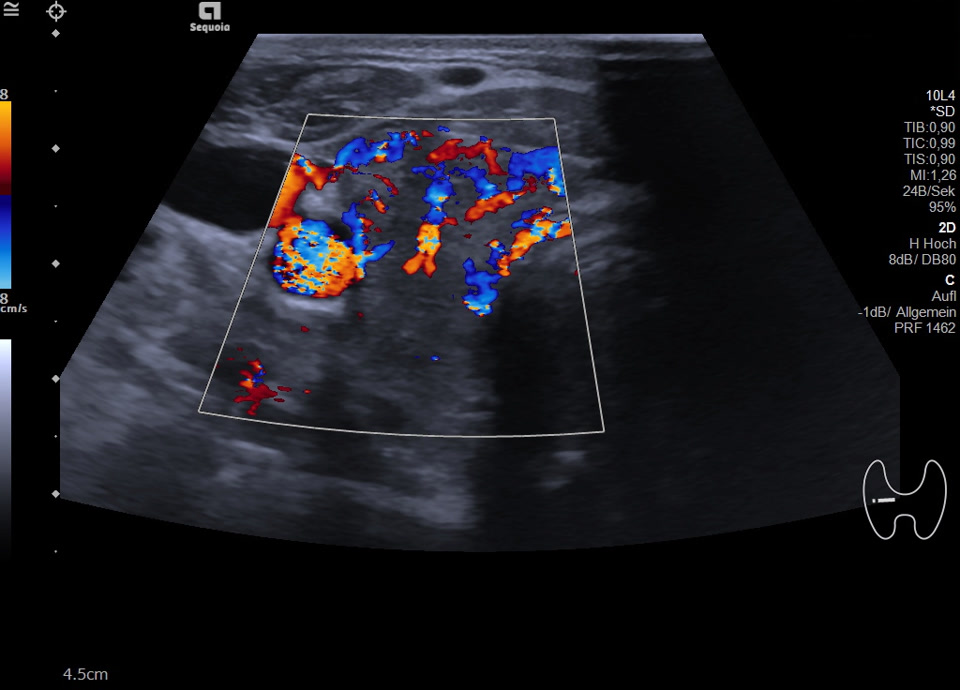

36-jähriger Patient mit Tremor, Tachykardie, Exophthalmus und Gewichtsverlust. Sonographisch stellt sich die Schilddrüse beidseits mit echoarmer inhomogener Parenchymstruktur dar. Gesamtvolumen 20,5 ml. Farbdopplersonographisch hypervaskularisiert. Laborbefunde: basales TSH erniedrigt, T3/fT4 erhöht, TRAK positiv. Befundkonstellation vereinbar mit M. Basedow. Unter Therapie mit Thiamazol und Propranolol beschwerdefrei. Bei Verlaufskontrolle zwei Jahre später sonographisch echoreiches minimal inhomogenes Parenchym bei normalem Volumen (15 ml).